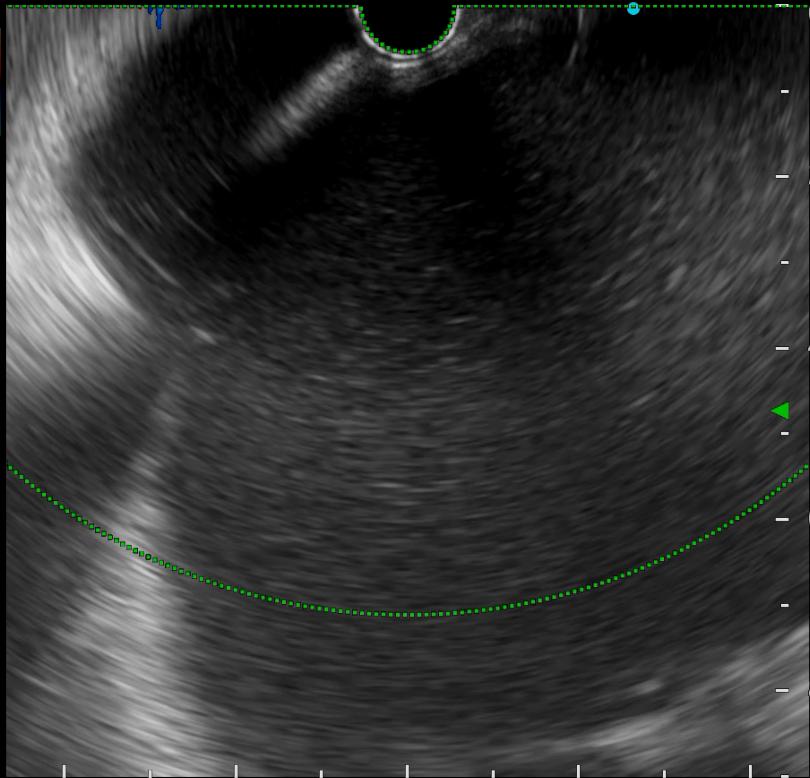

超声胃镜(胰腺巨大假性囊肿,囊腔内较多坏死物)